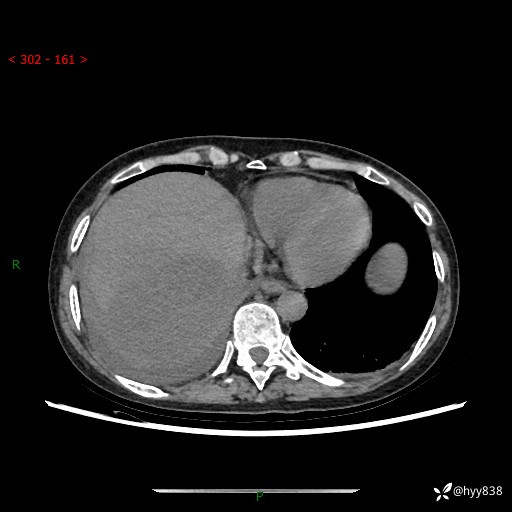

上腹部CT平扫